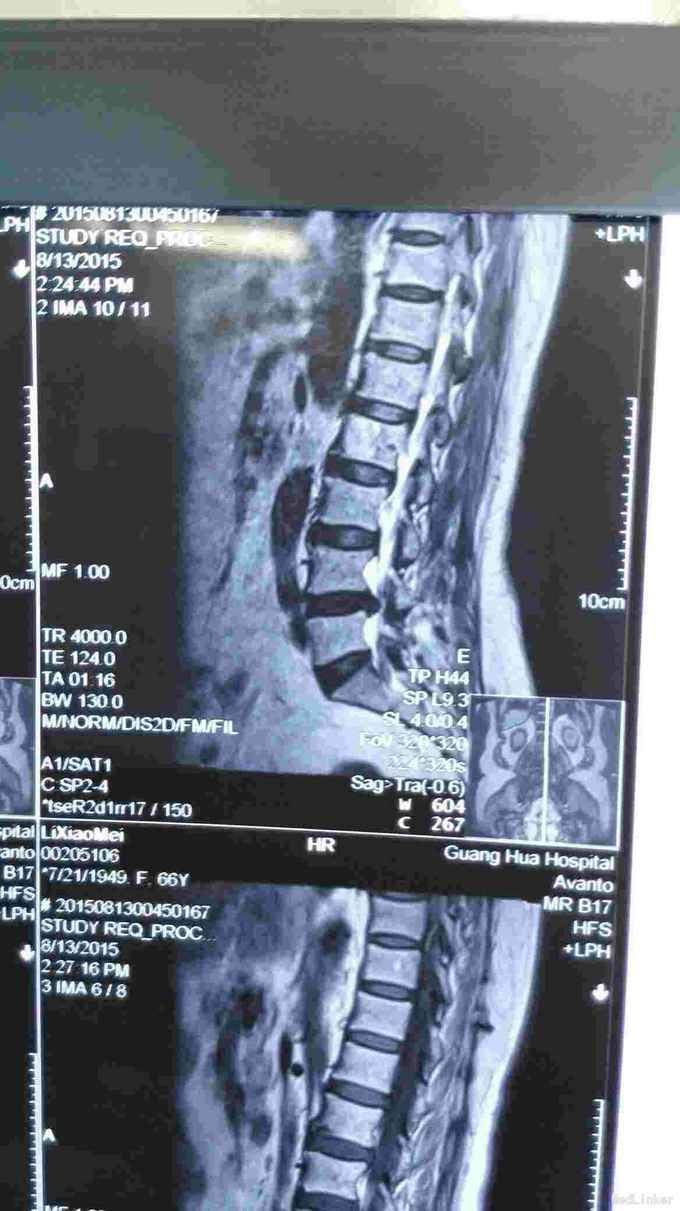

查体符合腰5神经根受压体征。腰椎CT、MRI提示腰4/5椎间盘突出,椎管狭窄。

考虑腰椎间盘突出伴椎管狭窄症。行椎间孔镜下髓核摘除,椎间孔成形。

术后患者症状消失。 目前脊柱内镜的应用越来越广泛,随着手术技术的进步可以很好解决部分椎管狭窄的问题。